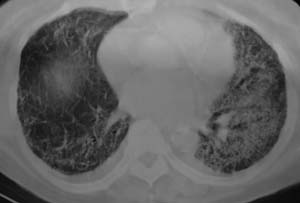

以下是引用liaizhi在2007-7-6 0:05:00的发言:[br]双肺纹理膜糊,沿纹理走行有班点状高密度影。考虑心衰并肺水肿。

以下是引用andymaomao在2007-7-5 22:23:00的发言:[br]双上肺明显,考虑心衰并肺水肿,双侧胸腔少量积液!另不除外肺泡蛋白沉着症及肺泡ca可能。[br]联想机制——心脏病(代偿期)--肺部淤血--后可能并感染致病情加重--抗炎治疗好转,但肺淤血严重,心功能失代偿--心衰而死亡!

以下是引用拾荒者在2007-7-6 13:06:00的发言:[br]支持:心衰,肺水肿及ards